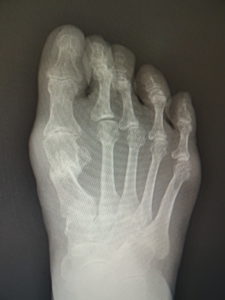

おおむね、外反角が30度以上になると、保存治療はもはやあまり有効ではありません。症状が強く、患者さんと良く吟味の上、希望されれば手術へと進みます。他に根治療法はないが、手術なら根治できます(図5)。ただMP関節の変性性変化があると、痛みや拘縮が残ることがあります。

(図5)

手術前 手術後4年

(図6)

手術前 手術後

真田理事長による手術の様子。外反母趾|症例 (左から 手術前、手術後、ワイヤ抜去後)